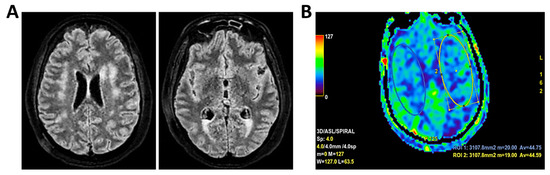

Background: Meningoencephalitis is a complex inflammatory condition of the CNS that can result in significant morbidity and mortality in critically ill adults. Accurate and timely neuromonitoring is essential for guiding management and improving outcomes. This study aimed to descriptively evaluate the prognostic value of early TCCD monitoring, particularly the pulsatility index, and its integration with conventional and perfusion MRI in patients with meningoencephalitis. Methods: We present an observational, retrospective, cohort study involving ten adult patients (median age 56 years, IQR 45.5–68.5; mean 55.9, range 35–76) with neurological syndromes caused by suspected or confirmed infectious meningoencephalitis. Etiologies included bacterial meningitis/meningoencephalitis (50%), viral meningoencephalitis (10%), neurotoxoplasmosis (10%), progressive multifocal leukoencephalopathy (10%), and undetermined origin (20%). Patients underwent TCCD and MRI within 24 h. In five cases, standard MRI sequences were acquired, while in the remaining five, perfusion imaging was performed using Arterial Spin Labelling (ASL). A favorable outcome was defined as survival with neurological recovery (Glasgow Outcome Scale > 5) at ICU discharge. Results: TCCD-derived PI provided valuable information on cerebral hemodynamics. PI values ≤ 1.25 were associated with favorable clinical outcomes and symmetrical MRI findings. Conversely, PI > 1.25 correlated with poor prognosis and often preceded MRI-detectable structural damage. When combined with ASL, PI mirrored the detected perfusion asymmetries and was associated with poor prognosis in fatal cases. Conclusions: Bedside TCCD can offer real-time assessment of cerebrovascular dynamics and, when integrated with conventional and ASL MRI, could enhance the understanding of pathophysiological processes in meningoencephalitis, supporting timely and informed decisions in neurocritical care.